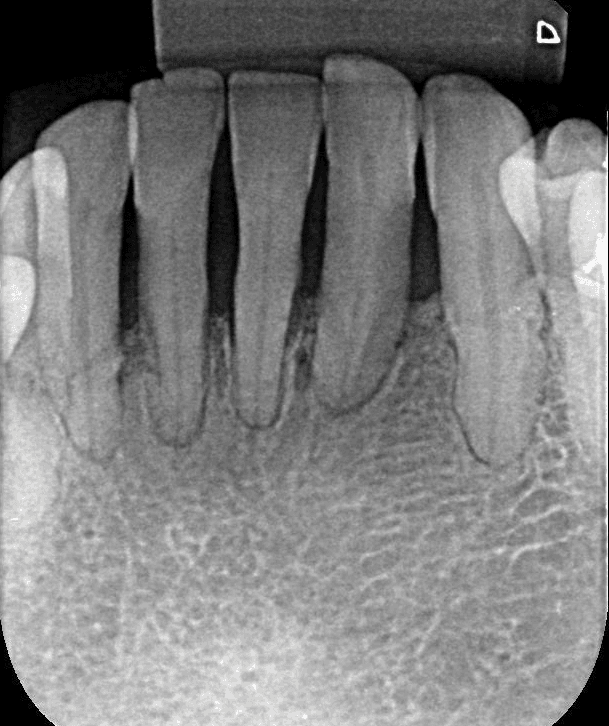

Perda Óssea Significativa:

A perda óssea ao redor dos dentes pode comprometer a capacidade do alinhador de mover os dentes de forma eficaz e segura.

A movimentação ortodôntica pode exacerbar essa mobilidade, o que aumenta o risco de complicações como a perda do dente ou uma piora da condição da gengiva.